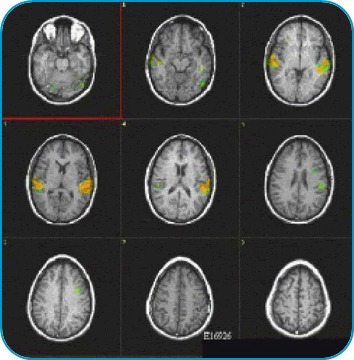

fMRI Studies (Functional Magnetic Resonance Imaging)

What is fMRI?

Functional magnetic resonance imaging (fMRI) is a development of MRI techniques that allows visualization of brain functions related to specific tasks. The study does not require any substance to be administered since it is based on the indigenous brain vascular response, requiring only cooperation for periods ranging from 15 to 60 minutes.

To date, several tasks have been utilized for mapping the brain cortex. Simple tasks include stimuli based on presentation of light, colors, tones, chords, music, syllables, movement of fingers and basic sensory perceptions. More complex and refined experiments have been implemented to map subtle cognitive functions. Currently, there is a vast armamentarium for mapping memory, attention, inhibition, face recognition, sensory discrimination, fear, etc.

However, most fMRI work has been directed in mapping language. Language mapping has been performed in children and adults. Reading, listening to meaningful text, generating words, making semantic decisions, are the most frequent paradigms described in the abundant current literature on fMRI. The technique has received ample acceptance among neuroscientists interested in epilepsy for the potential it has to become a tool to replace the Wada test.

Functional MRI is based on small signal changes that result from the following cascade of events. A task elicits activation in one or several brain areas. These areas increase their metabolic demands, suffer vasodilatation, and alter their levels of deoxyhemoglobin and oxyhemoglobin. Since deoxyhemoglobin is a paramagnetic molecule, it influences the phase of local proton-spins, altering the source signal that is converted into images. Therefore, the image is a representation of local changes of levels of deoxyhemoglobin, related to the brain region performing a task.

Although fMRI is almost risk-free, it cannot be performed in patients with claustrophobia, metal implants, wires and pace-makers. Patients with vagal nerve stimulators, or dental braces, may be included. However, some degradation of the images is expected.

Research and studies conducted by:

Dr. Nolan Altman and Dr. Byron Bernal of the Radiology Department

Clinical Cases Language Mapping Auditory Mapping 3D fMRI